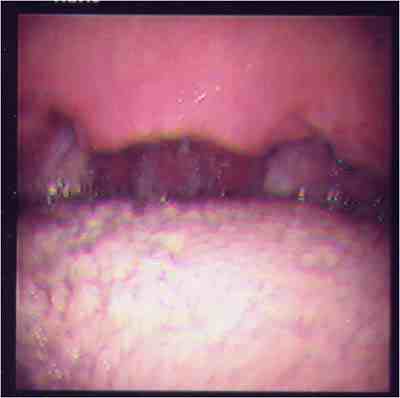

無呼吸の原因と考えられるポリープ様声帯に対し,喉頭微細手術を行い,

軟口蓋低位と狭い口峡に対し、UPPPを行った例。

手術前の咽頭手術後の咽頭

のどの奥が広くなっているのがわかります。